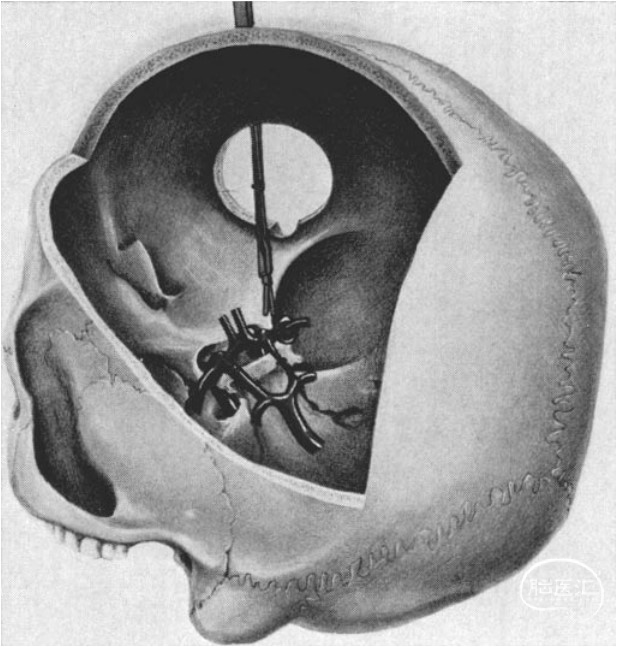

额外侧入路的艺术家视图。可见:额外侧入路是从前颅底外侧进入鞍区,并非直接沿着蝶骨嵴、外侧裂进入。

动脉瘤的示意图,以说明“非接触区域”与“工作区域”。